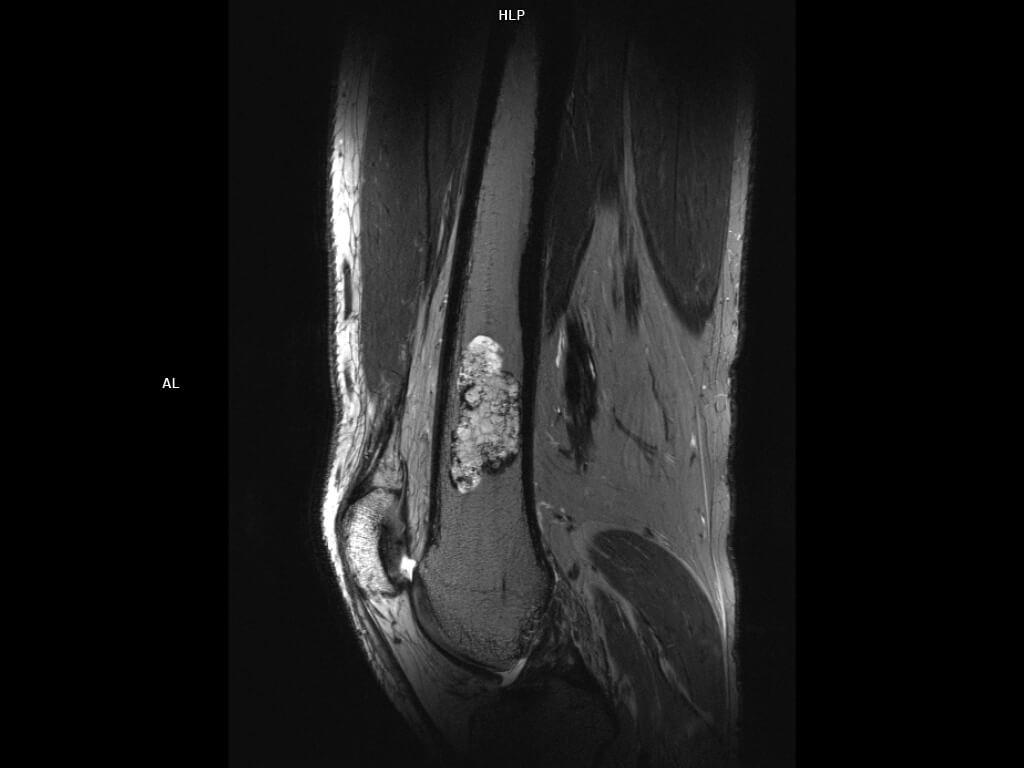

Sagittal T2 TSE 300um-MAGNETOM Terra

Sagittal T2 TSE 300um-MAGNETOM Terra/Coil-Knee 28/Resolution-1024/Scan Time-3:24/Aceleration-p2